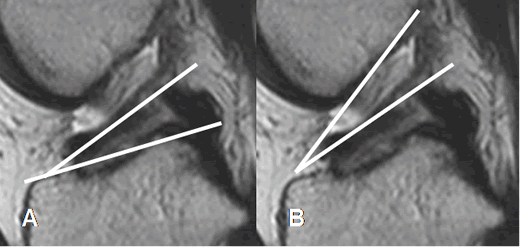

La ruptura completa del LCA, es diagnosticada mediante los signos primarios. (11). El principal, es la discontinuidad de las fibras (2, 35) y el otro es su orientación. Hay horizontalización, con disminución del ángulo de inclinación con la tibia, el cual es menor de 40º y el ángulo con la línea de Blumensaat, de vértice inferior y valor positivo mayor de 15º. (11). (Fig 100 y 101).

Fig 101. Ruptura del LCA.

A y B: RM sagital en T2. Signos de ruptura, con disminución del ángulo de inclinación tibial en A y ángulo con la línea intercondílea, de vértice inferior en B.